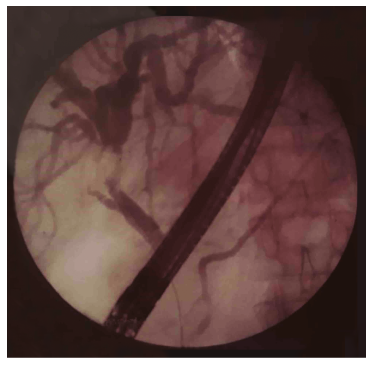

A gallbladder ultrasound showed multiple echogenic foci in the gallbladder consistent with cholelithiasis and intrahepatic biliary channel and choledochal duct dilation. An ERCP did not show an obvious common bile duct stone but did show a stricture in the common hepatic duct suggestive of cholangiocarcinoma (Figure 1).